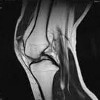

КТ опорно-двигательного аппарата

Компьютерная томография костно-мышечной системы. Диагностический метод исследования костной ткани с использованием направленного рентгеновского луча и компьютерного сканера. По сравнению с обычной рентгенографией КТ более точна при изучении патологических изменений позвоночника, костей и суставов; менее чувствителен к артефактам; позволяет выполнять последующую обработку трехмерного изображения. КТ костно-мышечной системы, помогает решать различные диагностические задачи: выявить сложные переломы и его осложнения; воспалительные, дегенеративно-дистрофические, опухолевые, пороки развития костной и хрящевой ткани; определить минеральную плотность кости; планировать хирургическое вмешательство или контролировать их результаты.